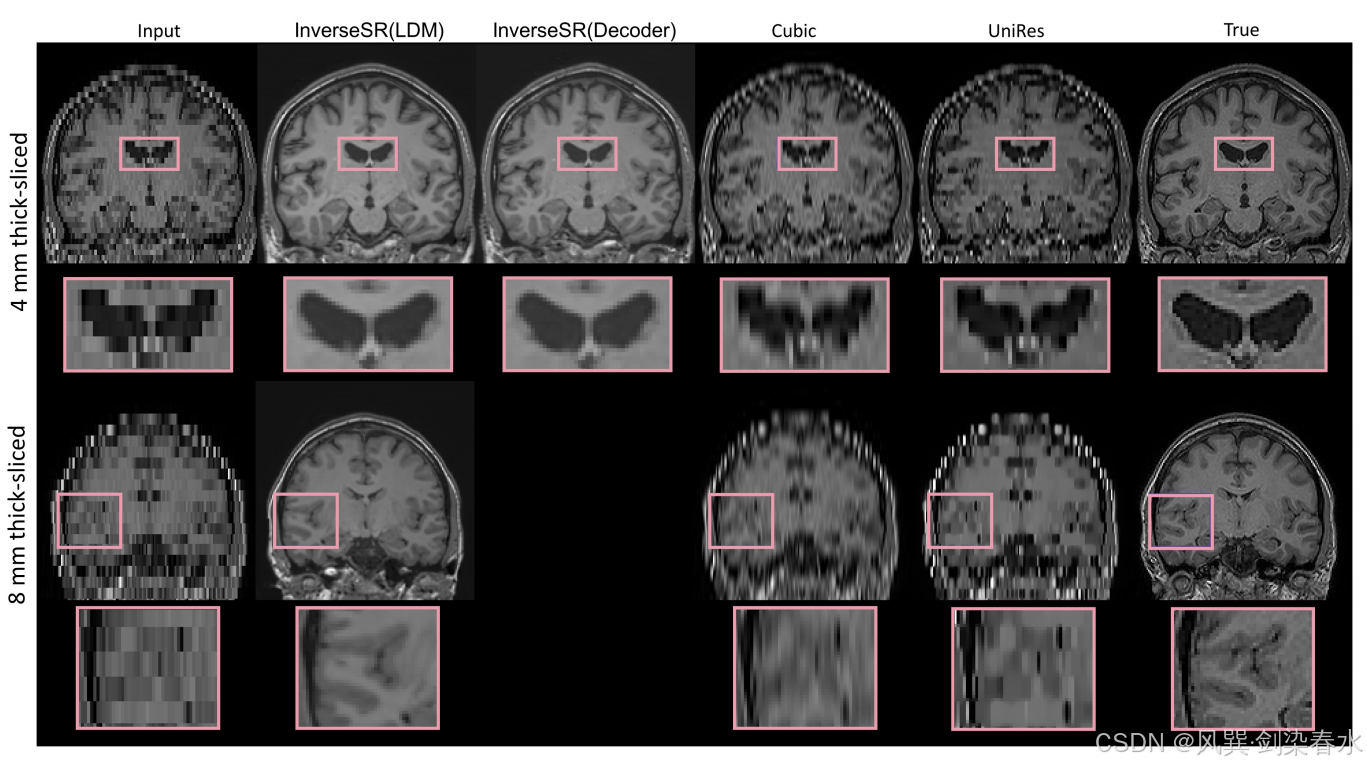

Figure 2 | InverseSR 和 Cubic 、 UniRes 基线在厚度为 4 mm 和 8 mm 的扫描上的定性结果: